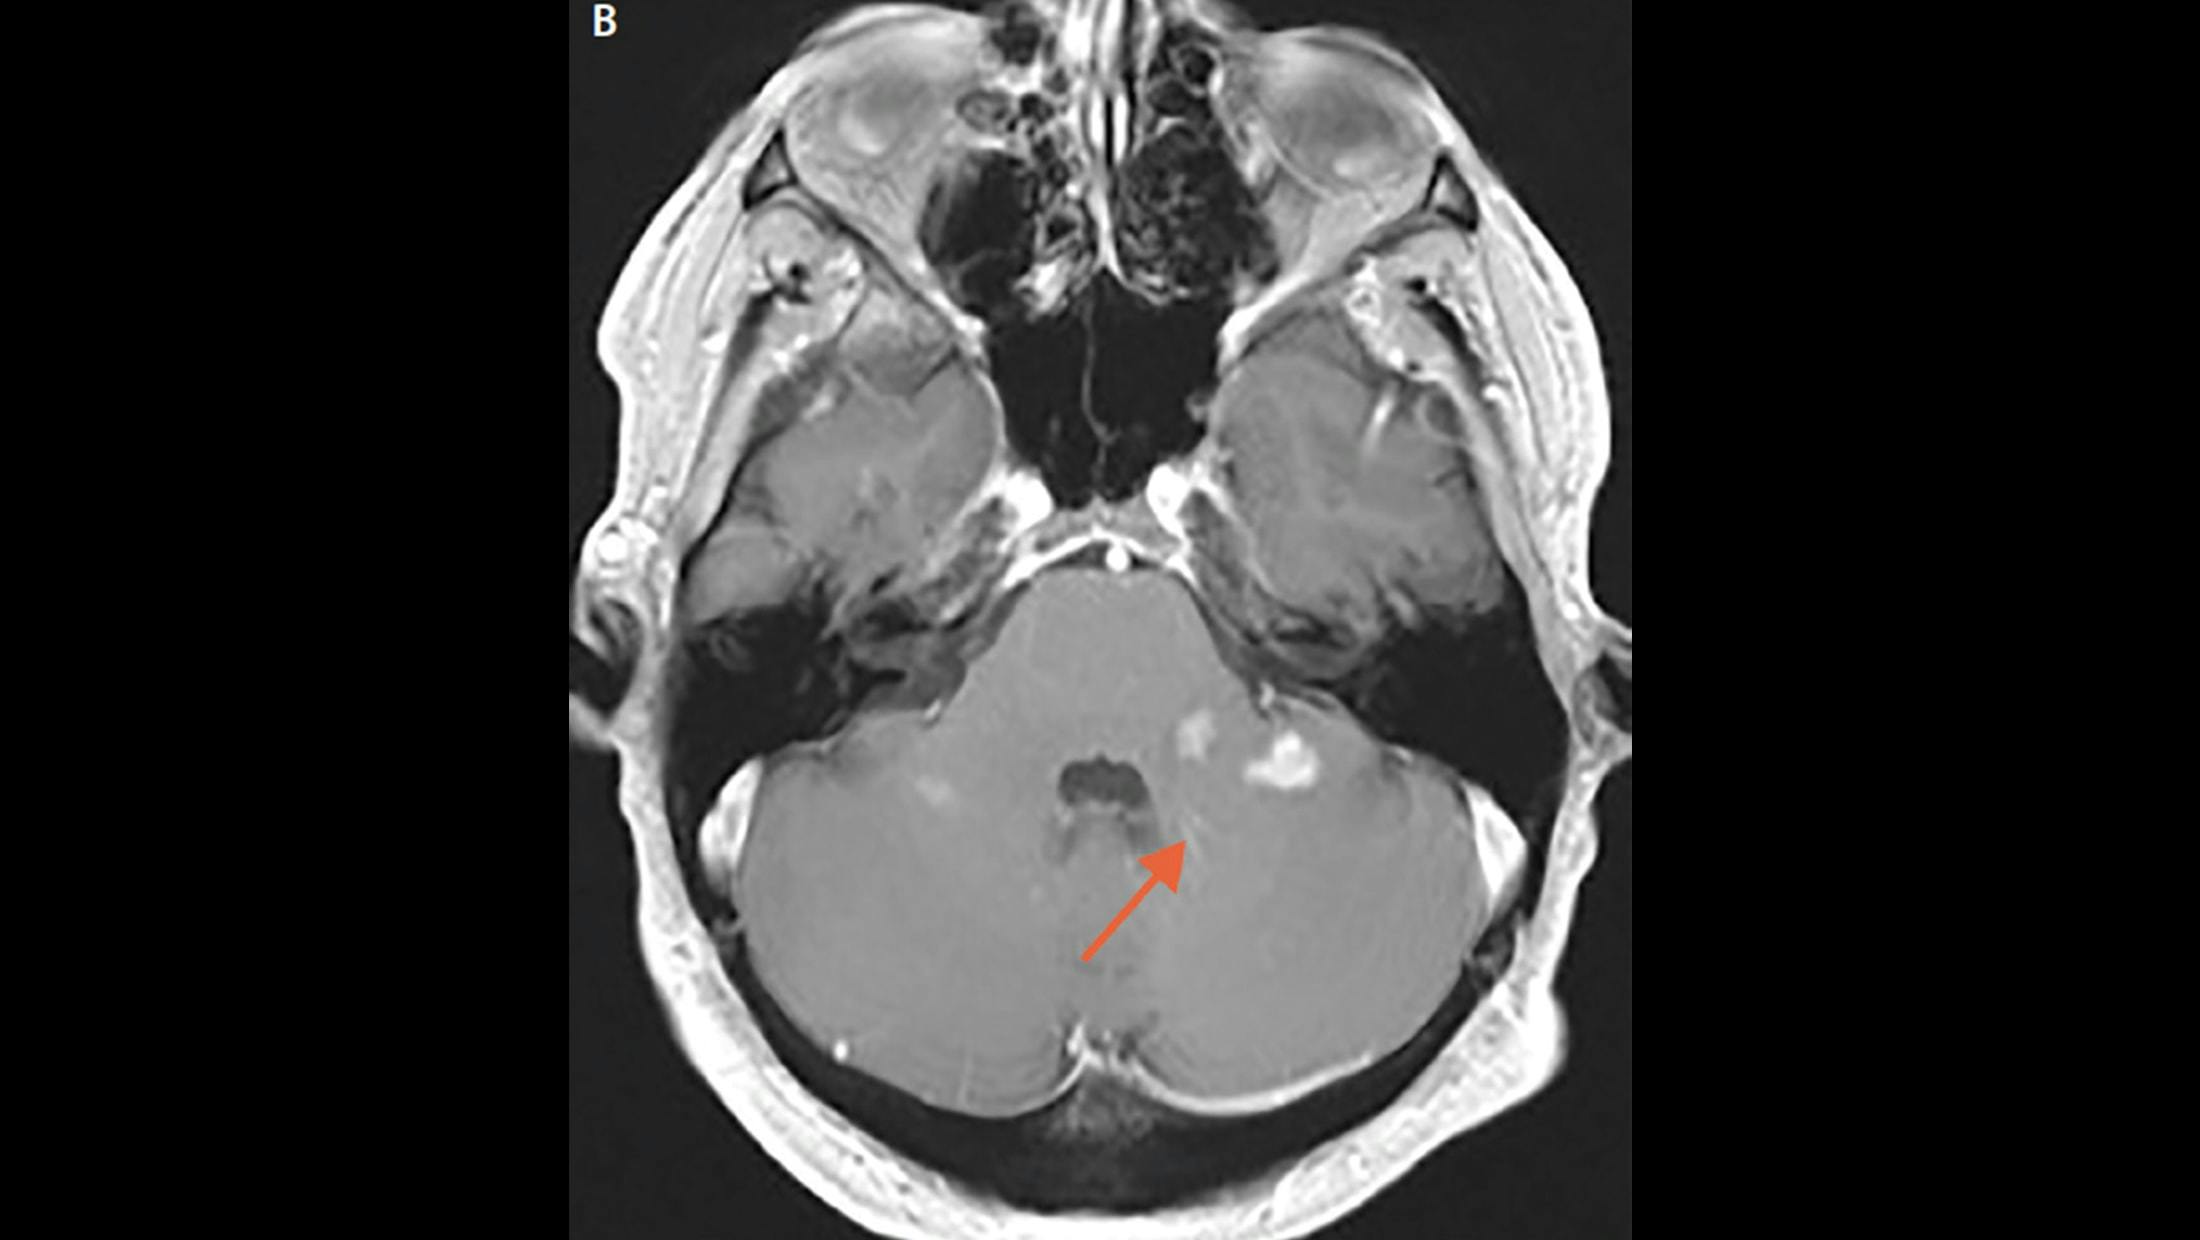

Brain MRI from Mr. L’s second hospitalization demonstrates resolution of the previously visualized right temporal lesion and leptomeningeal enhancement with new enhancing lesions both infratentorially bilateral optic neuritis.

Brain MRI from Mr. L’s second hospitalization demonstrates resolution of the previously visualized right temporal lesion and leptomeningeal enhancement with new enhancing lesions both infra- and supratentorially bilateral optic neuritis with greater enhancement in the right optic nerve compared with the left.